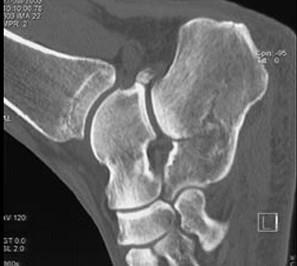

男,36岁,从高处摔下,脚部受伤,结合图像,最可能的诊断是 ( )A、舟状骨骨折B、楔骨骨折C、跟骨骨折D、骰骨骨折E、距骨骨折

问题 男,36岁,从高处摔下,脚部受伤,结合图像,最可能的诊断是 ( )

选项 A、舟状骨骨折 B、楔骨骨折 C、跟骨骨折 D、骰骨骨折 E、距骨骨折

答案 C